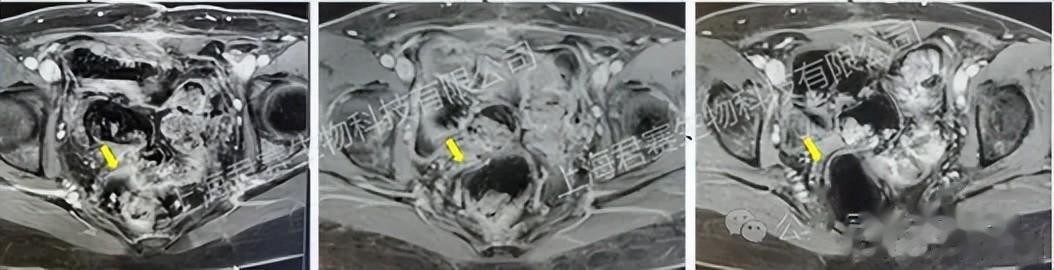

令她难以置信的是,仅仅在接受TIL细胞单次回输两个多月后,检查指标就显示肿瘤病灶完全消失,达到完全缓解(CR)。如今,四年过去了,她依然健康地生活着,回归了正常工作和生活。

受试者接受TIL回输前、回输后6周及回输后12周影像资料(图源官网,侵删)